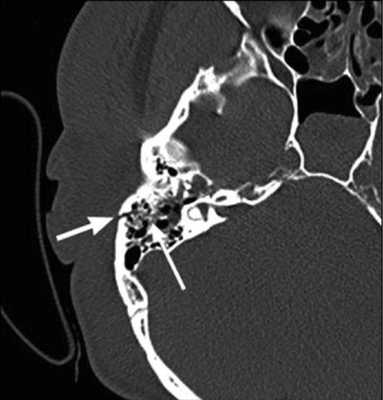

На КТ-снимке виден перелом пирамиды височной кости (указан стрелками)